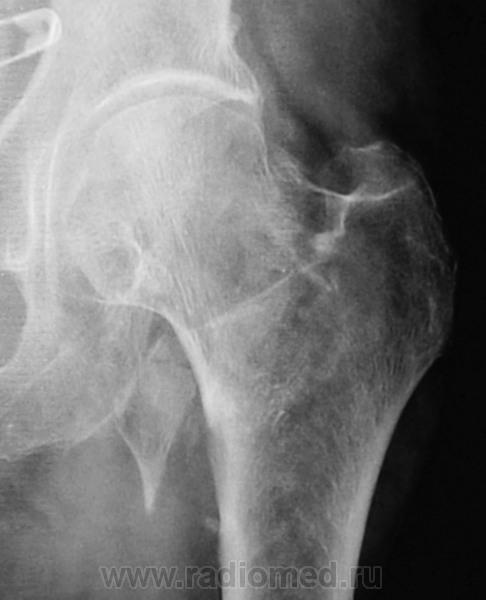

Пол пациента: Женский пол Тип патологии: Травма Область исследования: Скелетно-мышечная система Методы исследования: Rg Травма. Направлена на рентгенографию тазобедренного сустава https://radiomed.ru/sites/default/files/styles/case_slider_image/public/user/12/12.201201010053.jpg?itok=x97QZsTH ID:30719 Втр, 13/08/2013 - 18:18 #1 Sepsis Не на сайте Был на сайте: 1 год 8 месяцев назад Зарегистрирован: 13.12.2012 - 16:48 Публикации: 283 Отрывной перелом малого вертела. Втр, 13/08/2013 - 19:10 #2 Dima Не на сайте Был на сайте: 7 лет 2 месяцев назад Зарегистрирован: 05.08.2012 - 17:39 Публикации: 2467 По-моему черезвертельный с отрывом малого вертела Терпимость - это когда прощают чужие ошибки; такт - когда не замечают их. (Артур Шницлер) Втр, 13/08/2013 - 19:22 #3 maker4ik Не на сайте Был на сайте: 8 лет 7 месяцев назад Зарегистрирован: 19.10.2011 - 17:49 Публикации: 2682 Dima wrote: По-моему черезвертельный с отрывом малого вертела +1 Втр, 13/08/2013 - 19:50 #4 И.Бондаренко Не на сайте Был на сайте: 1 день 4 часа назад Зарегистрирован: 13.09.2011 - 22:55 Публикации: 9206 В основании шейки перелом, наверное чрезвертельный и отрыв малого вертела. Ср, 14/08/2013 - 13:20 #5 фатя Не на сайте Был на сайте: 4 года 2 месяцев назад Зарегистрирован: 13.02.2012 - 19:43 Публикации: 30 Чрезвертельный перелом с отрывом малого вертела фкар

Отрывной перелом малого вертела.

По-моему черезвертельный с отрывом малого вертела

В основании шейки перелом, наверное чрезвертельный и отрыв малого вертела.

Чрезвертельный перелом с отрывом малого вертела